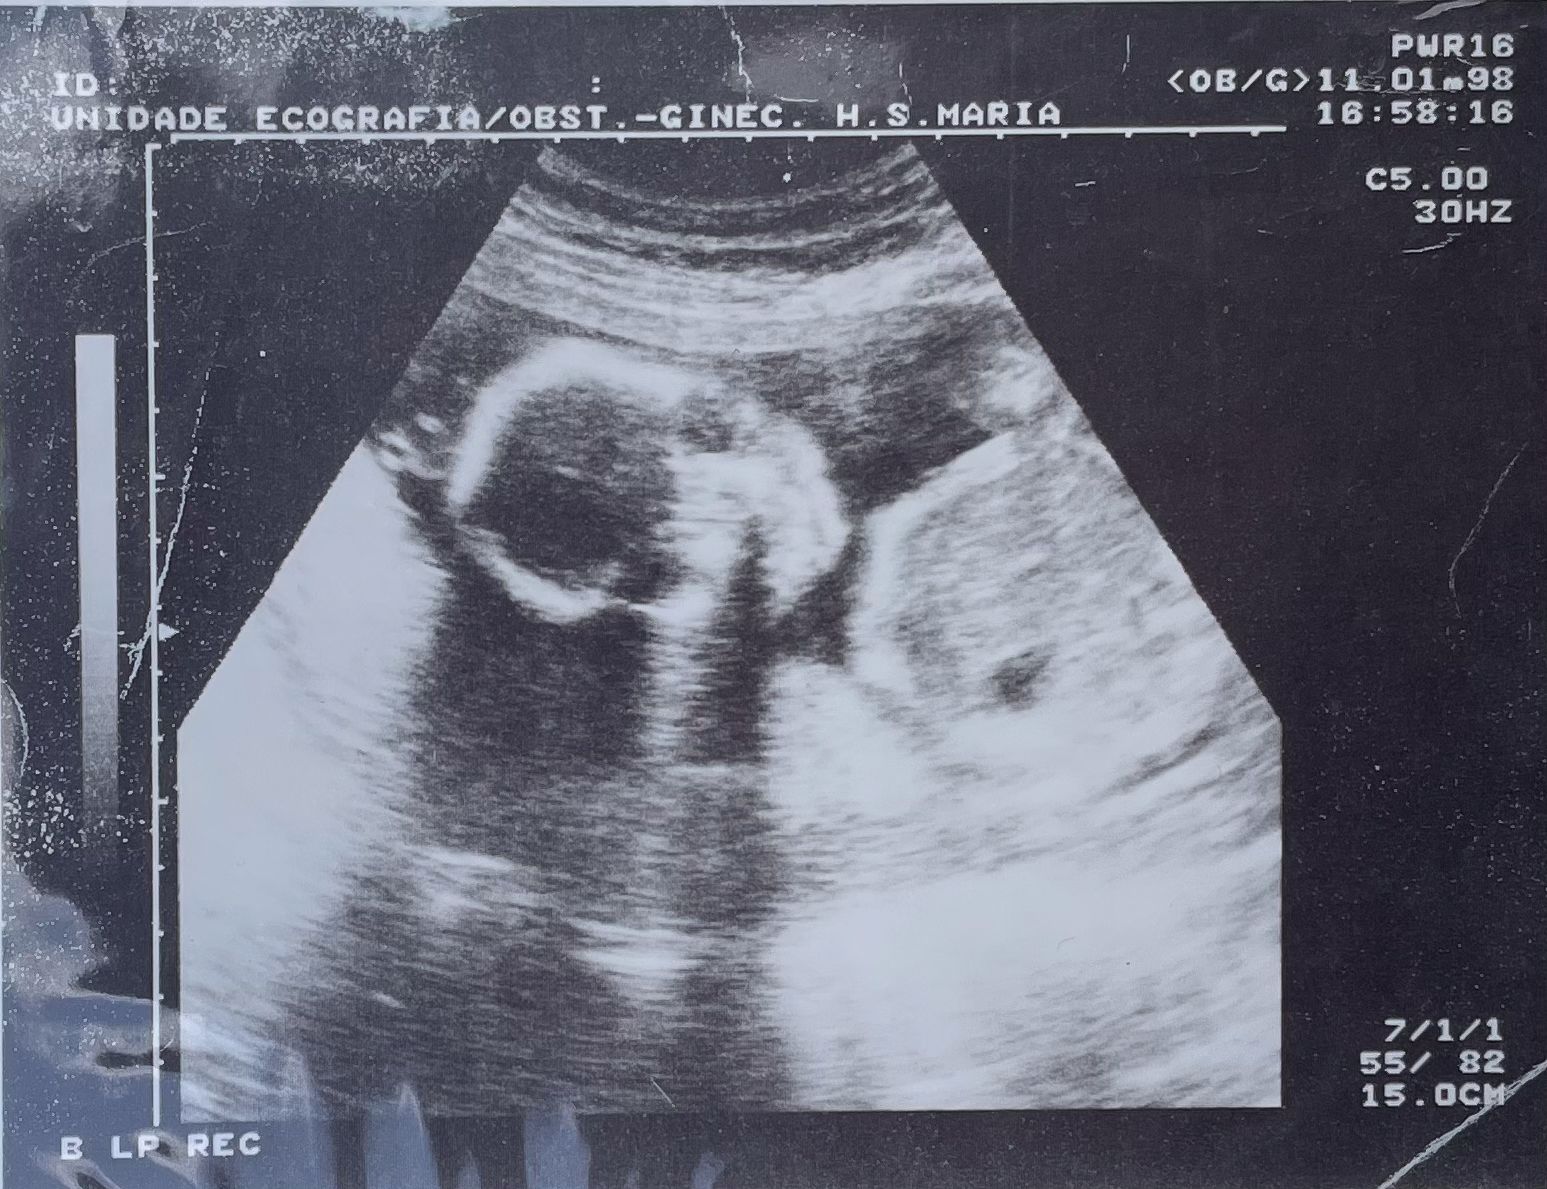

Aos seis meses de gestação, teve de ser internada. A baixa estatura, que contrastava com a barriga de dilatação avançada, tornava a sua mobilidade praticamente nula. Os médicos concluíram que o parto teria de ser prematuro e iniciaram as sessões diárias de fisioterapia na tentativa de prolongar ao máximo a gravidez. Sandra nasceu pouco mais de dois meses depois do internamento e necessitou de cuidados intensivos em incubadora.